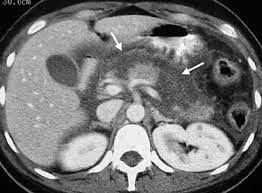

Η αξονική τομογραφία δίνει μια καλή αξιολόγηση των παγκρεατικών αλλοιώσεων και την ύπαρξη περιπαγκρεατικής νέκρωσης και εξιδρωμάτων. Ο όγκος των εξιδρωμάτων και η έκταση της νέκρωσης του αδένα έχουν προγνωστική αξία.